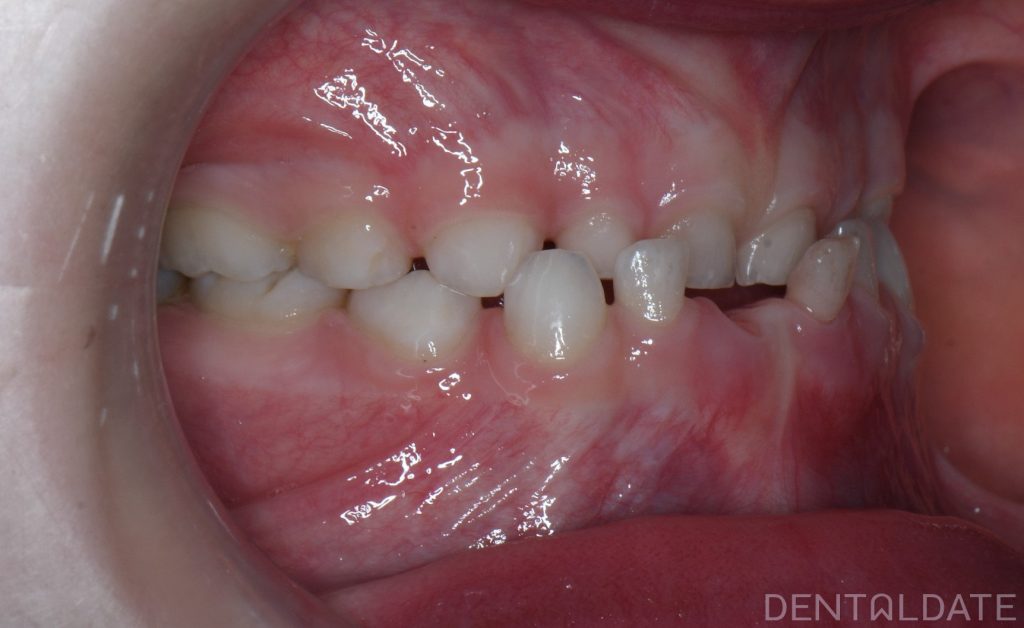

The patient’s mother came in for a consultation, reporting that her child was experiencing difficulty chewing and rarely smiled.

A key goal of children orthodontic treatment is to normalize physiological growth and development.